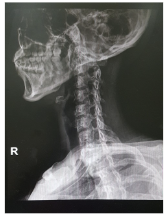

목디스크 증상 원인 치료방법 등 목 디스크 관련 정보에 대해 알아보도록 하겠습니다. 목 디스크는 목의 디스크가 탈출하거나 튀어나와서 신경이나 척수를 압박하는 질환입니다. 목 디스크는 잘못된 자세나 과도한 힘, 교통사고 등으로 인해 발생할 수 있으며, 목뿐만 아니라 어깨, 팔, 손가락 등에도 통증이나 저림감을 유발할 수 있습니다.